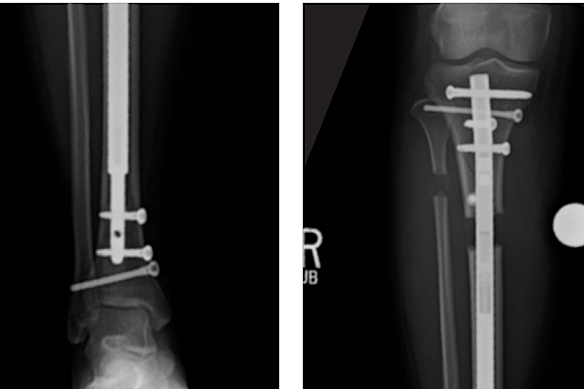

Surgical nails have been an alternative to the Ilizarov method since the 1990s where large nails are inserted into the bone and external remote controls or magnets move the nail externally to cause fractures, eliminating the metal cage and associated infection risks.

Paley invented the Stryde Nail with manufacturer Nuvasive in 2018, which used stainless steel instead of titanium, allowing heavier patients to weight-bear immediately after surgery.

Promotional material depicting the use of the Stryde nail developed by Dror Paley.